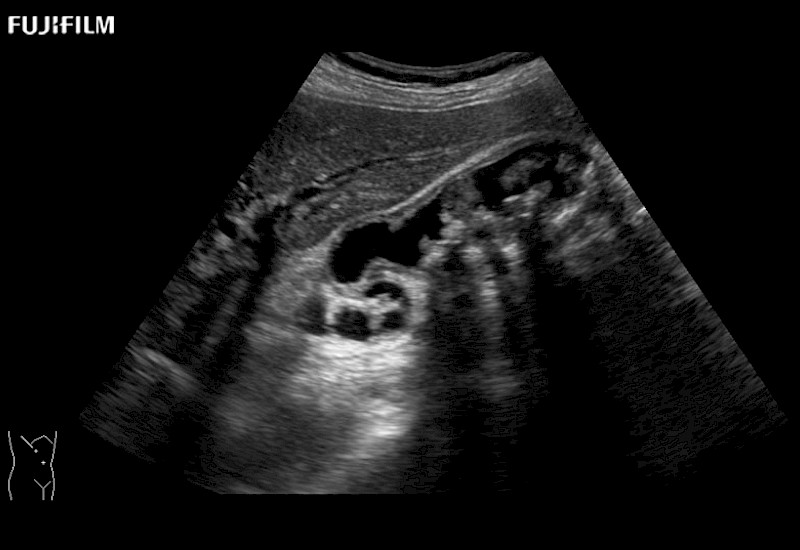

Learn moreFujifilm Healthcare continues to listen to the experts, our neurosurgeons, by developing an ultrasound system specifically designed for the Operating Room.

Guidance is the fundamental purpose for all of our surgical ultrasound technology. Fujifilm Healthcare is committed to designing tools that help neurosurgeons navigate inside the human body and provide the necessary information to immediately make critical surgical decisions.

With the ARIETTA Precision the next level of surgical ultrasound is here.